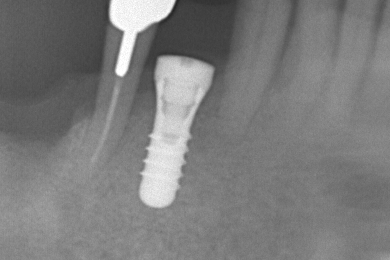

重度虫歯からのインプラント・入れ歯治療(*^-^*)